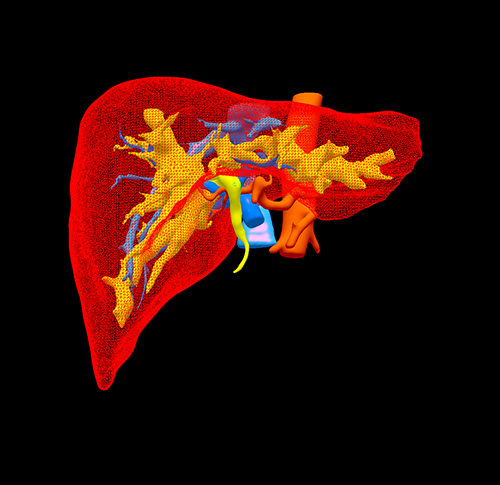

IV型胆管癌---胆管癌根治(左半肝+尾状叶切除)